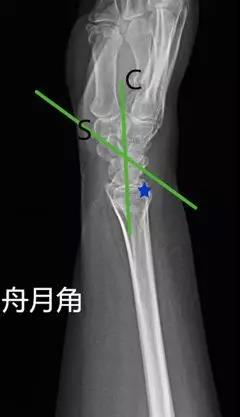

- 舟月角:在腕关节侧位片舟骨与月骨(近端与远端)中轴线的夹角。

- 正常值:30°~60°

- 临床意义:舟月角>70°提示腕背伸不稳,<30°提示腕掌屈曲不稳;>60°或移位>1mm,需要对舟骨进行切开复位内固定;舟月间距<3mm,间距>3mm提示舟月韧带撕裂。